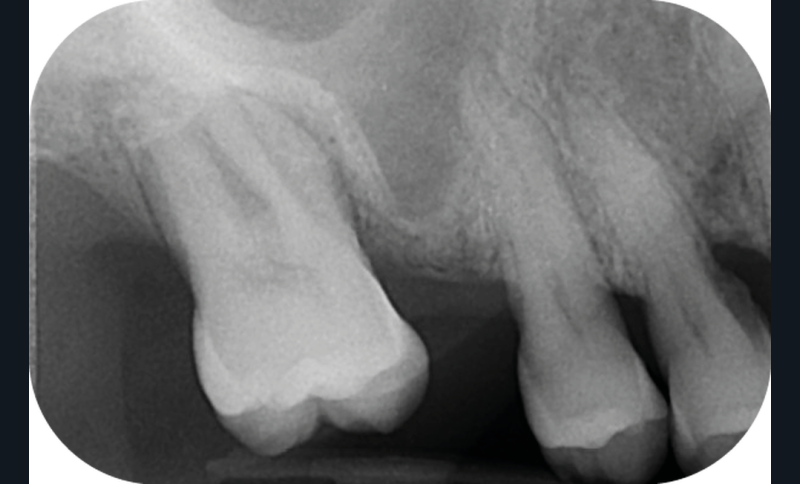

La version des dents distales peut aussi avoir des conséquences parodontales désastreuses : sur un parodonte réduit, une hypermobilité peut se développer, une poche parodontale peut aussi apparaître. Chez un patient parodontal, un « effet domino » est possible, des extractions non compensées diminueront donc le pronostic des dents restantes (fig. 7 à 9).

Le principe de protection mutuelle implique que les dents postérieures protègent les antérieures lors de la mastication. Des extractions non compensées de molaires, par exemple, entraîneront une hypersollicitation des antérieures et une usure importante du fait du principe de calage ainsi qu’un risque de perte de dimension verticale (fig. 10 à 13).